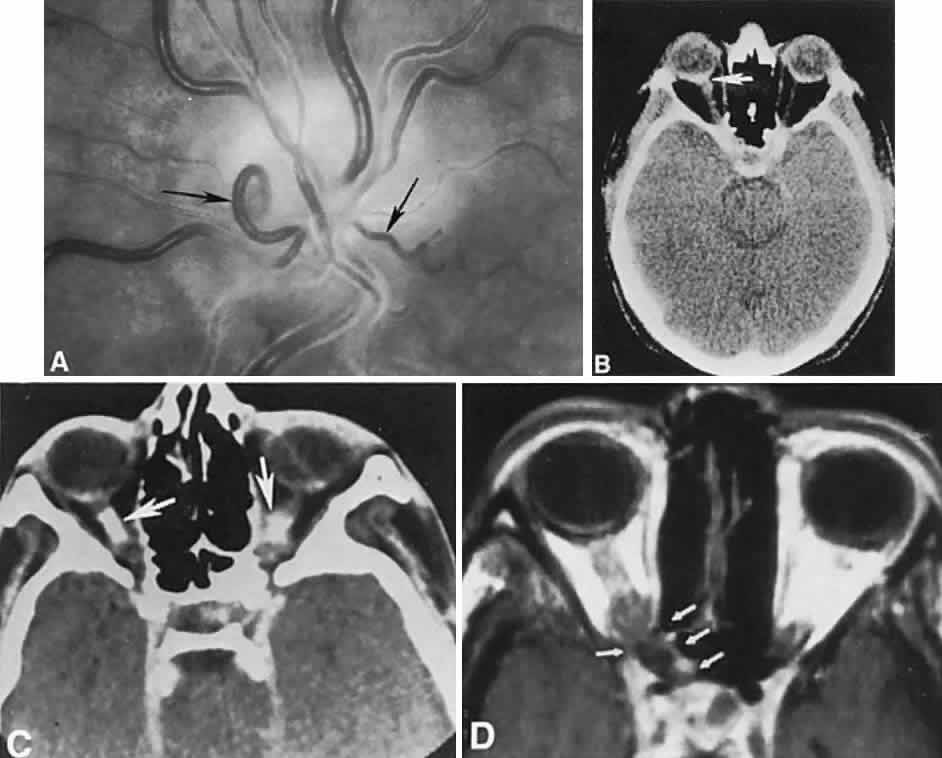

The retinal variety may be admixed in a person who suffers the more conventional attacks of migraine. It is presumed that vasospasm in the retinal circulation determines transient hypoxia, perhaps somewhat similar to the visual cortical event. On rare occasions, the fundus has been examined during typical retinal migraine episodes, and arterial constriction has been described. Wolter and Burchfield106 photographically documented such an episode and demonstrated mild “retinal edema”; vessel narrowing is also evident (Fig. 8). Fortunately, permanent complications of retinal migraine are rare. These may take the form of central retinal artery occlusion or ischemic papillopathy (see Volume 2, Chapter 16); nerve fiber bundle visual field defects may be demonstrated (Fig. 9).

Fig. 8. Retinal migraine. A. During amaurotic episode. Note the dusky appearance of the fundus, increased retinal sheen (possibly edema), and dark narrowed veins (arrows). The disc is also hyperemic. B. Fundus after episode. Compare paired arrows. (Courtesy of Dr. J. Reimer Wolter)

Fig. 9. An 18-year-old student with recurrent episodes of left retinal migraine. After a typical attack, he noted an inferior field defect. A. Fundus shows a defect in the superior arcuate nerve fiber bundle (between arrows: compare fiber layer below disc). B. Visual field defect corresponds to a retinal nerve fiber layer defect.